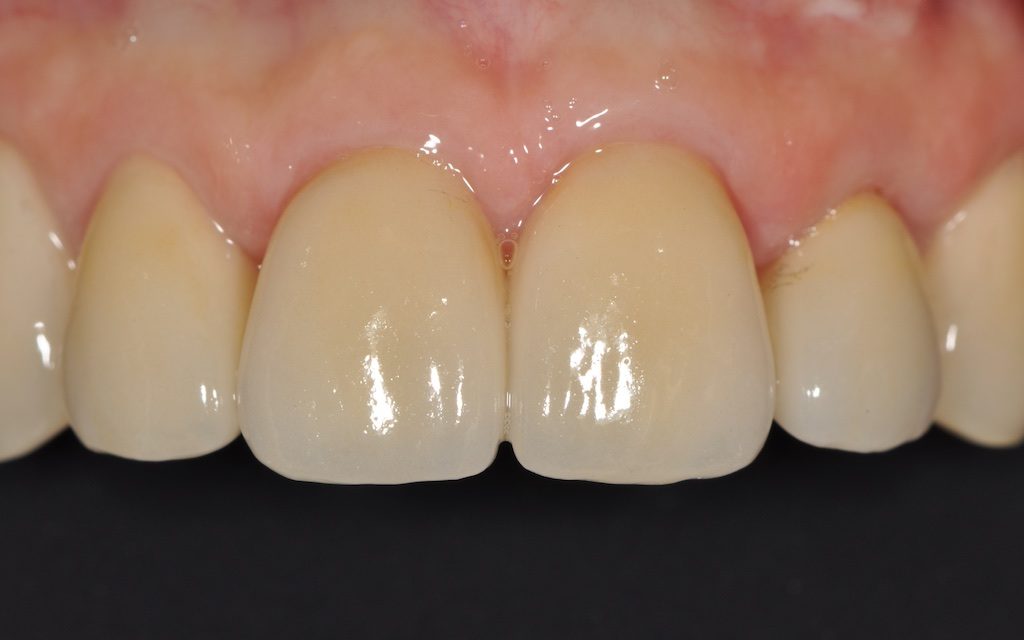

Fig. 8a à 8j : Résultat final

AVANT/APRÈS :